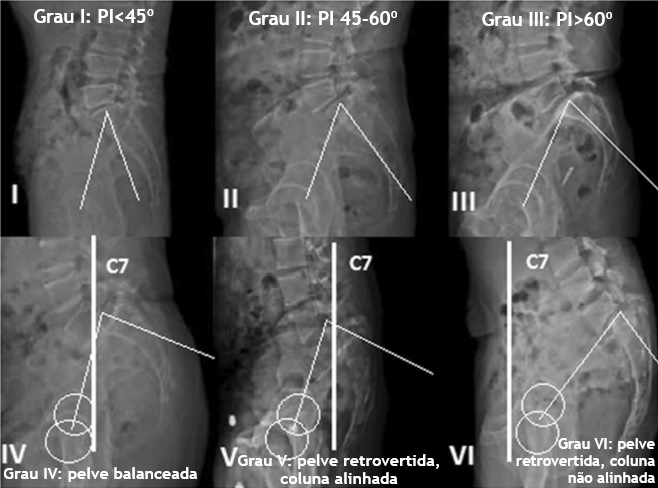

Classificação do Spinal Deformity Study Group (SDSG):

Esta classificação considera o grau de deslizamento, a incidência pélvica e o alinhamento sacropélvico e espinhal. Primeiro, determina-se o grau de deslizamento, se baixo (Meyerding 1 ou 2) ou alto grau (Meyerding 3 ou 4). Em seguida se faz a medida dos parâmetros sacropélvicos, como SS, PT e PI.

Na espondilolistese de baixo grau (Meyerding 1 e 2), 3 subgrupos são divididos baseados no valor de PI (incidência pélvica):

– Grupo I: PI <45º;

– Grupo II: PI entre 45 e 60º;

– Grupo III: PI >60º.

Na espondilolistese de alto grau (Meyerding 3 e 4 ) ) também são subdividos 3 grupos:

– Grupo IV: pelve balanceada;

– Grupo V: pelve retrovertida, coluna alinhada;

– Grupo VI: pelve retrovertida, coluna desalinhada.